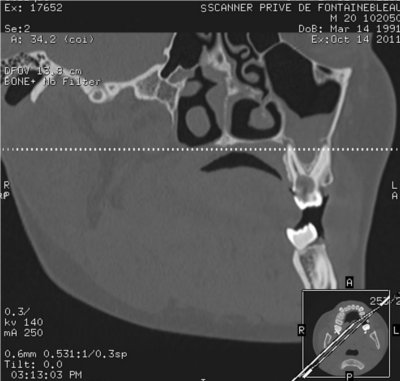

SCANNER DENTAIRE (DENTALSCANNER)

Les nouvelles générations de scanner permettent de faire une acquisition d’un volume global d’une partie du corps et de travailler à l’intérieur de ce volume en isolant une structure anatomique donnée et de l’explorer dans tous les plans de l’espace.

Grace à la technique de seuillage il est possible de dissocier progressivement les dents des structures osseuses environnantes dans le volume donné.